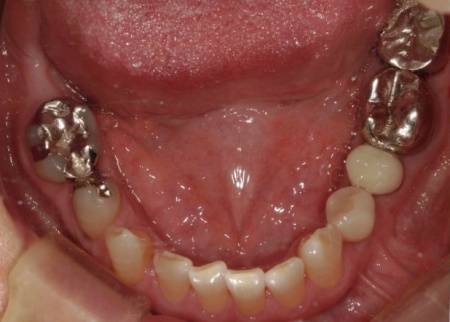

70代女性 歯根が割れた左下奥歯を抜きインプラントで噛み合わせを回復させた症例

レントゲン撮影を行って詳しく拝見したところ、左下奥歯(第1小臼歯)の歯根が割れていました。

まず、周辺組織に負担をかけないよう配慮しながら、慎重に左下奥歯(第1小臼歯)を抜きます。

抜歯後は骨や歯茎の回復を待ち、口腔内の状態が安定したことを確認して、インプラント埋入手術へ進みました。

後日、インプラントと骨がしっかりと結合したら、精密な型取りを行い、被せ物を作製します。

最後に完成した被せ物を装着し、痛みや違和感がないか、見た目や噛み合わせに問題がないかを確認して、治療を終了しました。